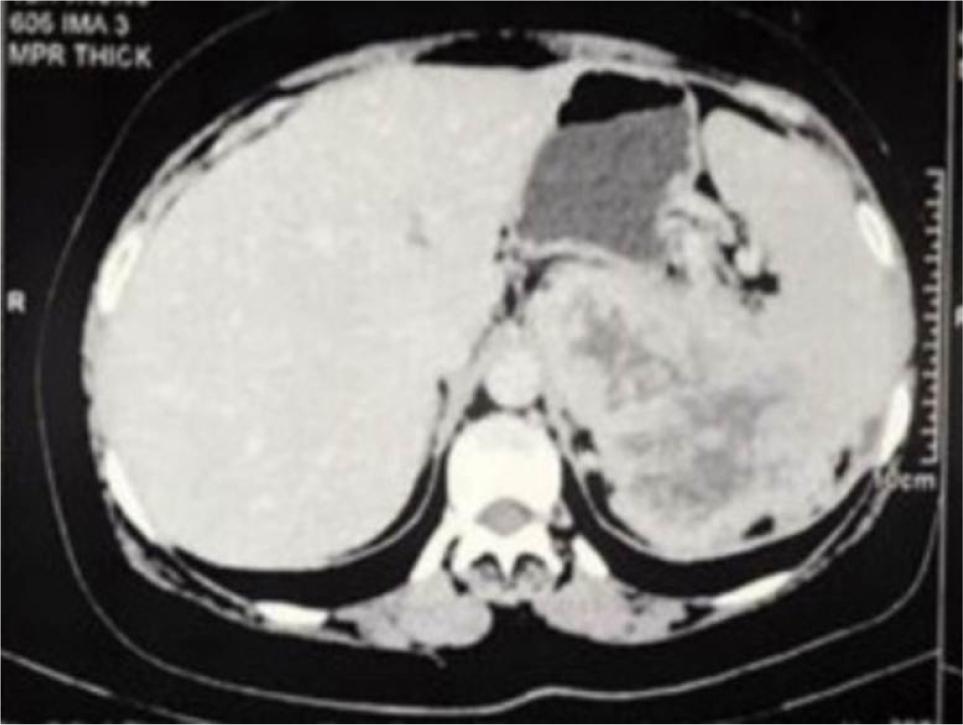

A 50-year-old man presented with left loin pain. An ultrasound, followed by a CT scan, revealed a 17.5 cm left renal mass invading the left suprarenal gland, spleen, pancreatic tail, and a part of the diaphragm. He had excellent performance status and no distant metastases. Radical nephrectomy through chevron incision under epidural block with general anesthesia was performed. Over a 2-hour operation, the entire mass was removed including the kidney, adrenal gland, spleen, pancreatic tail, and diaphragmatic fibers. There was a large chain of para-aortic lymph nodes that was removed as well. The estimated blood loss was 300 mL, and no blood transfusions were required. Chest tube was inserted and removed after 48 h. Histological examination revealed Grade 4 clear cell RCC with extension into the spleen, pancreatic tail, and diaphragmatic fibers. Invasion of main renal vein and pelvicalyceal system was identified. There was neither sarcomatoid differentiation nor lymphovascular invasion. All surgical margins were negative. The resected lymph nodes were reactive with no evidence for cancer (Stage T4N0). Preoperatively, Hgb was 12 g/dL and eGFR was 85 mmol/L. On the first postoperative day, Hgb was 10 g/dL and eGFR dropped to 60 mmol/L, and these values were nearly stable during hospital admission. Four weeks post operation, the patient was reviewed. His wound had healed well, with no complications. Chest X-ray was normal. Hgb did rise to 13 g/dL, and eGFR was 80 mmol/L. The patient was discharged after a 3-day uneventful hospital stay. Six months’ CT scan did not show any evidence for cancer recurrence. We referred the patient to medical oncology team, and we agreed on surveillance, and systemic therapy was not offered. Within that short term follow-up, the patient recovered well and did not show evidence for residual or recurrent cancer. Patient’s consent was obtained for data collection and publication. Ethical approval was not required. Figure 1 is a CT section showing the advanced renal mass and Figure 2 is an operative image for the resected kidney, spleen and pancreatic tail.

Figure 2: The resected en bloc mass showing the kidney, spleen, and tail of pancreas.